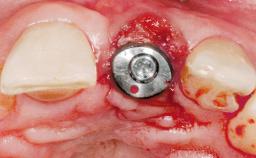

A 30-year-old female patient had lost tooth 21 and was referred to our clinic for consultation and treatment. Due to advanced apical infection, tooth 21 had been extracted two months earlier at another clinic and an acrylic-resin tooth had been bonded to the adjacent teeth. The patient desired implant treatment to avoid any damage to the adjacent natural teeth. While the patient had no history of any systemic disorder, she was a heavy smoker and exhibited medium to advanced periodontitis in the entire jaw. After the initial treatment to achieve a pocket probing depth of less than 4 mm and no bleeding on probing, a decrease in the height of the papillae mesial and distal to the extraction site and overall gingival recession were observed.

Type of Implants One-Piece|Reduced-Diameter

Attachment One-Piece|Reduced-Diameter

Soft Tissue Grafting Simultaneous

Abutment Type CAD/CAM